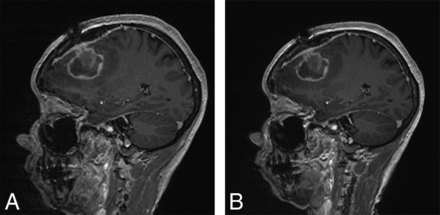

Most of the MPRAGE postcontrast evaluations reported that the sequences were equivalent. However, there was a trend among the observers to find more artifacts on the 10-minute sequence, though the difference was not statistically significant (P = .08). The presence of these artifacts did not influence the overall diagnostic quality (P = .66) (Fig 2).

Sagittal postcontrast MPRAGE images from a 53-year-old woman with history of breast cancer showing postoperative findings after resection of a brain metastasis. Ten-minute sagittal 3D MPRAGE (A) and standard sagittal 3D MPRAGE (B) images both show comparable diagnostic quality.